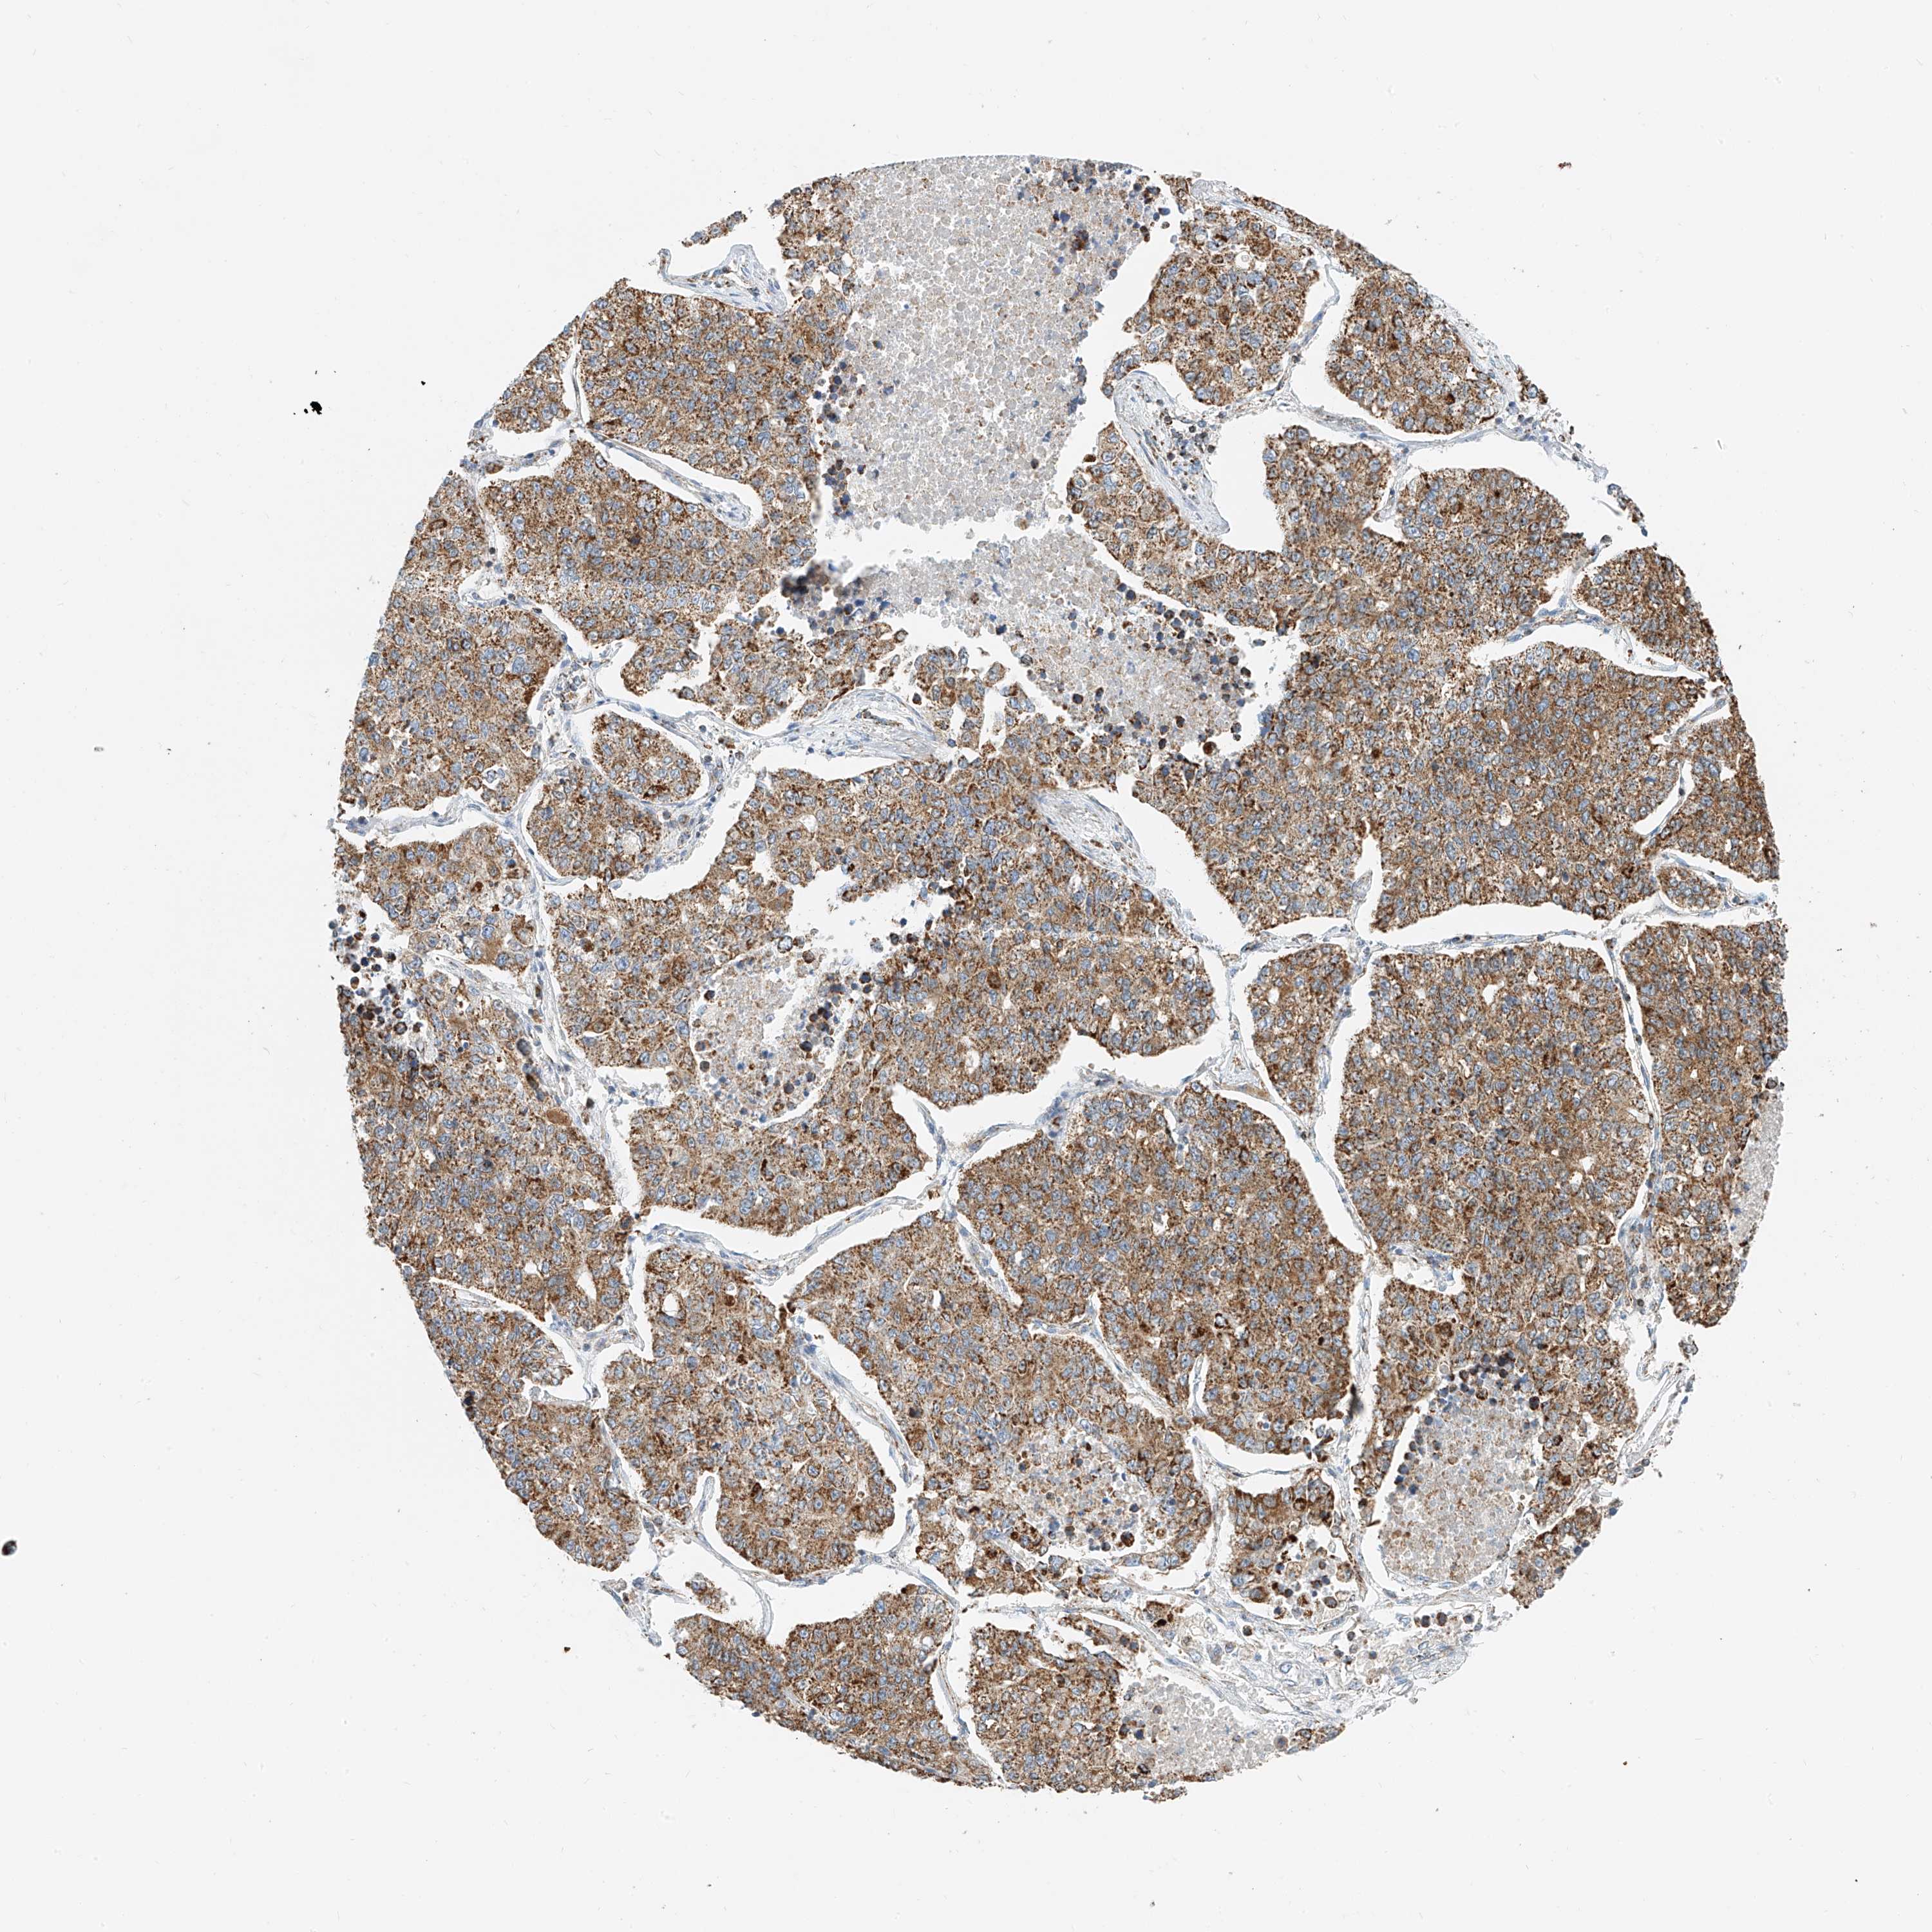

CANCER LUNG CANCER Show tissue menu

Lung cancer

Human cancer

Lung adenocarcinoma

Lung squamous cell carcinoma